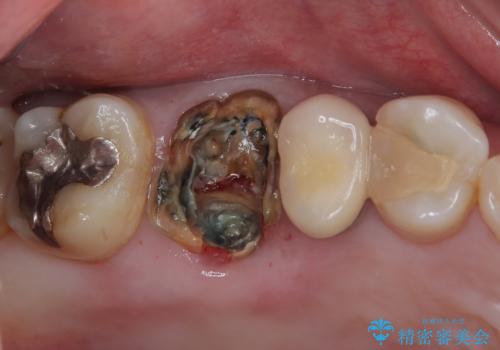

詰めている材料を外したところ、目視で確認できるほど割れており、要抜歯との説明をし、インプラント治療を行うこととしました。

来院されるまではインプラント治療を躊躇されていましたが、抜歯即時埋入により、単回の外科処置で治療が終えられることのメリットを理解され、インプラントによる補綴治療を行いました。

スムーズに治療を終えることができました。